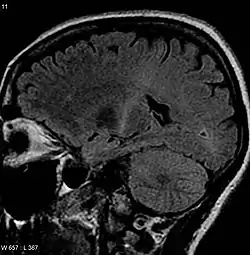

![]() This MRI (parasagittal استعادة السائل الموهن بالانقلاب) demonstrates increased T2 signal within the posterior part of the محفظة غائرة and can be tracked to the subcortical white matter of the قشرة حركية, outlining the سبيل قشري نخاعي, consistent with the clinical diagnosis of ALS.[2][2][3] This MRI (parasagittal استعادة السائل الموهن بالانقلاب) demonstrates increased T2 signal within the posterior part of the محفظة غائرة and can be tracked to the subcortical white matter of the قشرة حركية, outlining the سبيل قشري نخاعي, consistent with the clinical diagnosis of ALS.[2][2][3] | |

و لأن أعراض هذا المرض تتشابه مع اعراض الكثير من الامراض الأخرى التي يمكن معالجتها، لذلك يجب اجراء الفحوصات الازمة لاستبعاد الامراض الأخرى.واحدة من هذه التجارب هو رسم العضلات الكهربى، وهو تقنية تسجيلية خاصة حيث يتم تسجيل نشاط العضلة الكهربى. بعض النتائج المعينة لهذا الاختبار ترجح وجود المرض.[84] وهناك اختبار آخر مشهور الذي يقيس سرعة التوصيل قي الاعصاب. بعض النتائج الغير طبيعية في هذا الاختبار ترجح وجود أمراض أخرى، على سبيل المثال، إذا كان المريض يعانى من التهاب الاعصاب الطرفية (تلف الأعصاب الطرفية) أو خلل في العضلات (مرض في العضلات) وليس مرض تصلب العضلات الجانبى.[85] قد يطلب الطبيب عمل الرنين المغناطيسي، وهو إجراء غير تدخلى يستخدم المجال مغناطيسي وموجات الراديو للحصول على صورا تفصيلية للمخ والحبل الشوكي.[86] وعلى الرغم أن نتائج الرنين المغناطيسي طبيعية في هذا المرض إلا أنه قد يساعد على كشف غيره من المشاكل التي قد تكون سببا لهذه الاعراض، مثل ورم الحبل الشوكي، والتصلب المتعدد، انزلاق غضروفى في فقرات الرقبة، ناصور النخاع الشوكى أو تقوس فقرات الرقبة.[87][88]